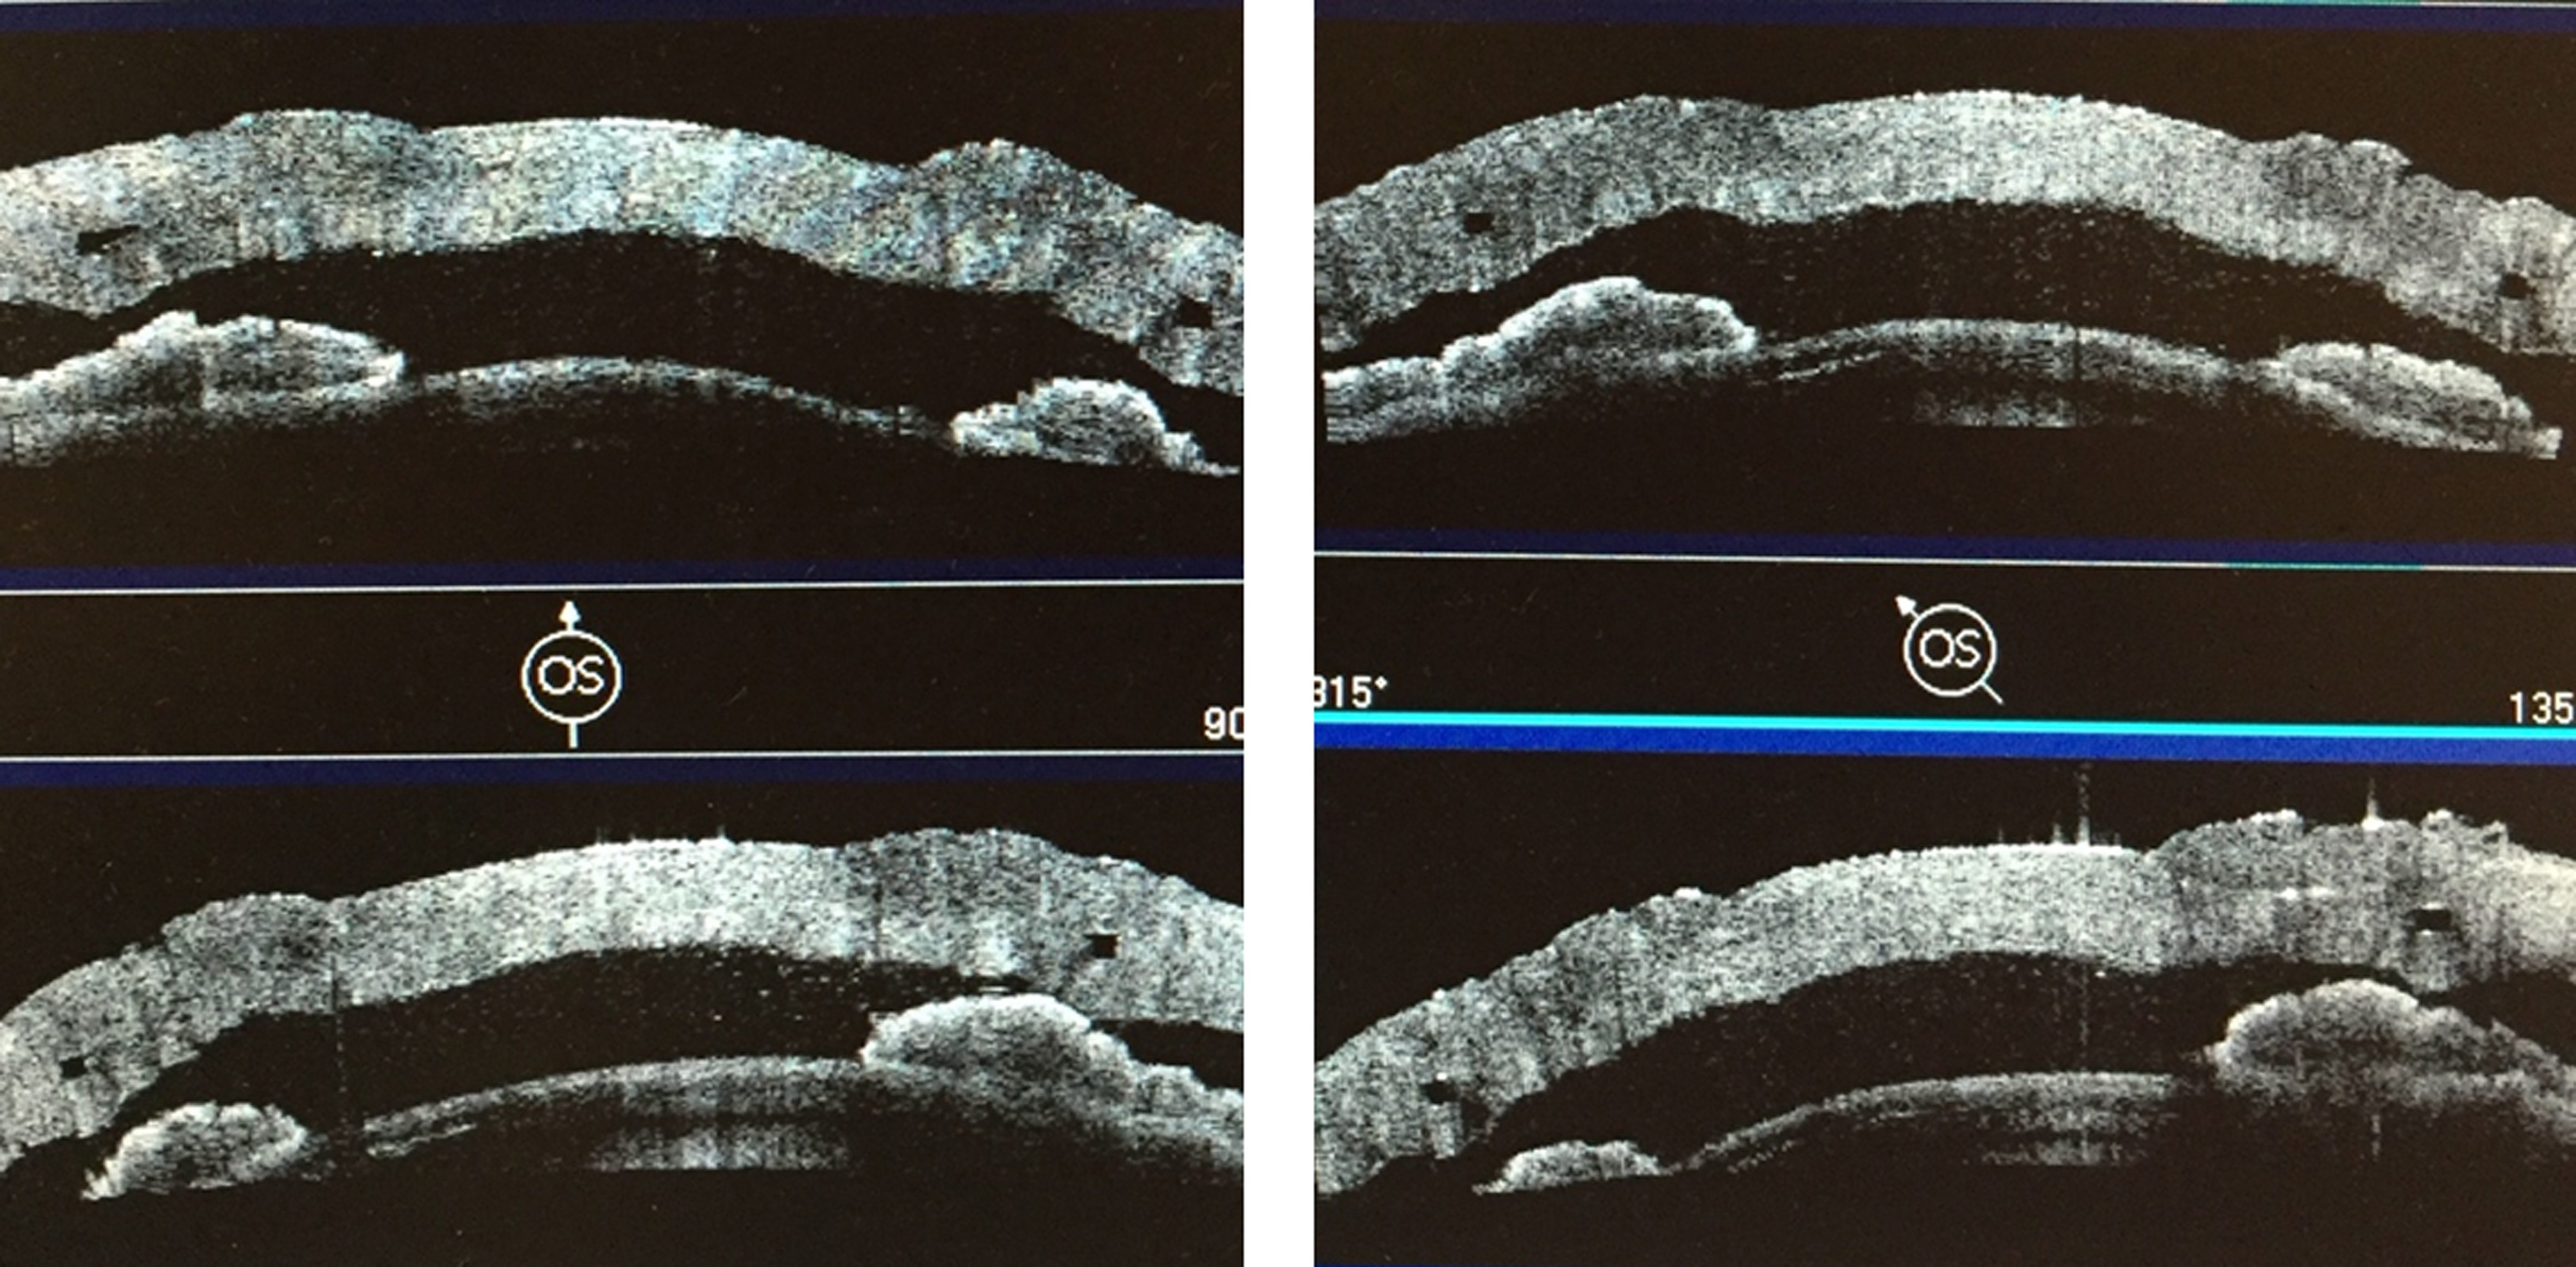

Результаты проведения модифицированной технологии сквозной фемто-кератопластики с имплантацией ИСК в эксперименте проводили с помощью оптической когерентной томографии переднего отрезка глазного яблока Visante ОСТ (Carl Zeiss Meditec, Германия). В ходе исследования оценивали положение ИСК (рис. 5), равномерность его залегания по глубине во всех сегментах.

Равномерность залегания ИСК оценивали путем определения глубины расположения его верхнего края в строме кадаверного глаза в 8 равномерно удаленных друг от друга точках по данным оптической когерентной томографии (ОКТ) (рис. 6), в среднем этот параметр составил (445,6 ± 14,9) мкм.

Рис. 5. Положение интрастрамального кольца в 4 меридианах в строме роговицы кадаверного глаза по данным оптической когерентной томографии

Рис. 6. Измерение глубины залегания ИСК по данным ОКТ

Экспериментальное моделирование на кадаверных глазах позволило разработать технику предлагаемой модифицированной сквозной фемто-кератопластики с имплантацией ИСК и алгоритм хирургического вмешательства [5]. По данным ОКТ переднего отрезка глазного яблока, интрастромальное кольцо располагалось равномерно во всех сегментах, без признаков его смещения. Использование параметров работы ФСЛ, разработанных совместно с производителем ФСЛ для проведения кератопластики, позволили выполнить качественное отделение роговичного диска без применения механического усилия во всех случаях.